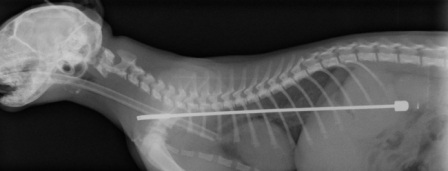

Chiếc ăng-ten xuyên từ cổ họng xuống dạ dày

(Dân trí) - Chú mèo Alphie ở Anh đã vô tình nuốt phải một đoạn đoạn ăng-ten TV dài hơn 15cm vào thực quản. Nhưng chú mèo đã may mắn thoát chết sau khi được các bác sĩ phẫu thuật lấy đoạn ăng-ten đó ra.

Alphie sau đó đã được các bác sĩ thú ý tiến hành phẫu thuật lấy đoạn ăng-ten ra.

Ca phẫu thuật diễn ra thành công tốt đẹp. Các bác sĩ cho biết, đó là trường hợp bất thường nhất họ từng gặp.